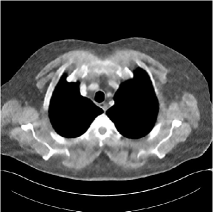

Refer to caption WavResNet [11]Refer to caption WavResNet [11]Refer to caption WavResNet [11]Refer to caption Momentum-Net (SimpleCNN)Refer to caption Momentum-Net (SimpleCNN)Refer to caption Momentum-Net (SimpleCNN)Refer to caption Momentum-Net (SimpleCNN-RSN)Refer to caption Momentum-Net (SimpleCNN-RSN)Refer to caption Momentum-Net (SimpleCNN-RSN)Refer to caption Momentum-Net (Dn-RSN)Refer to caption Momentum-Net (Dn-RSN)Refer to caption Momentum-Net (Dn-RSN)Refer to caption ReferenceRefer to caption ReferenceRefer to caption Reference

Fig. 3: Three examples (from top to bottom) of the reconstructed testing images using Momentum-Net with SimpleCNN (the second column), with SimpleCNN-RSN (the third column), and with Dn-RSN (the fourth column). The compared WavResNet denoised images are shown in the first column, and the reference images are in the fifth column. See their FBP images in Fig. 4.

Fig. 2 shows that the proposed Momentum-Net with SimpleCNN decreases RMSE dramatically in the first 30 layers, and tends to converge in 50 layers. The Momentum-Net reduces the mean RMSE value by 4.5 HU and gives smaller standard deviations in RMSE, compared to WavResNet, as reported in Table 1. This implies that the proposed Momentum-Net with SimpleCNN can improve both the accuracy and stability of low-dose CT image reconstruction than a state-of-the-art image denoising deep NN, WavResNet. The proposed Momentum-Net with SimpleCNN better removes noise and streak artifacts than WavResNet. It also provides clearer reconstructions of some details; see, in Fig. 3, the boundaries shown in the zoomed region at the top-right corner in the first example, the arrow pointed structures in zoomed areas of the second example, and the arrow pointed tissues in the left zoomed region in the third example.

3.3 Momentum-Nets involving RSN-based training